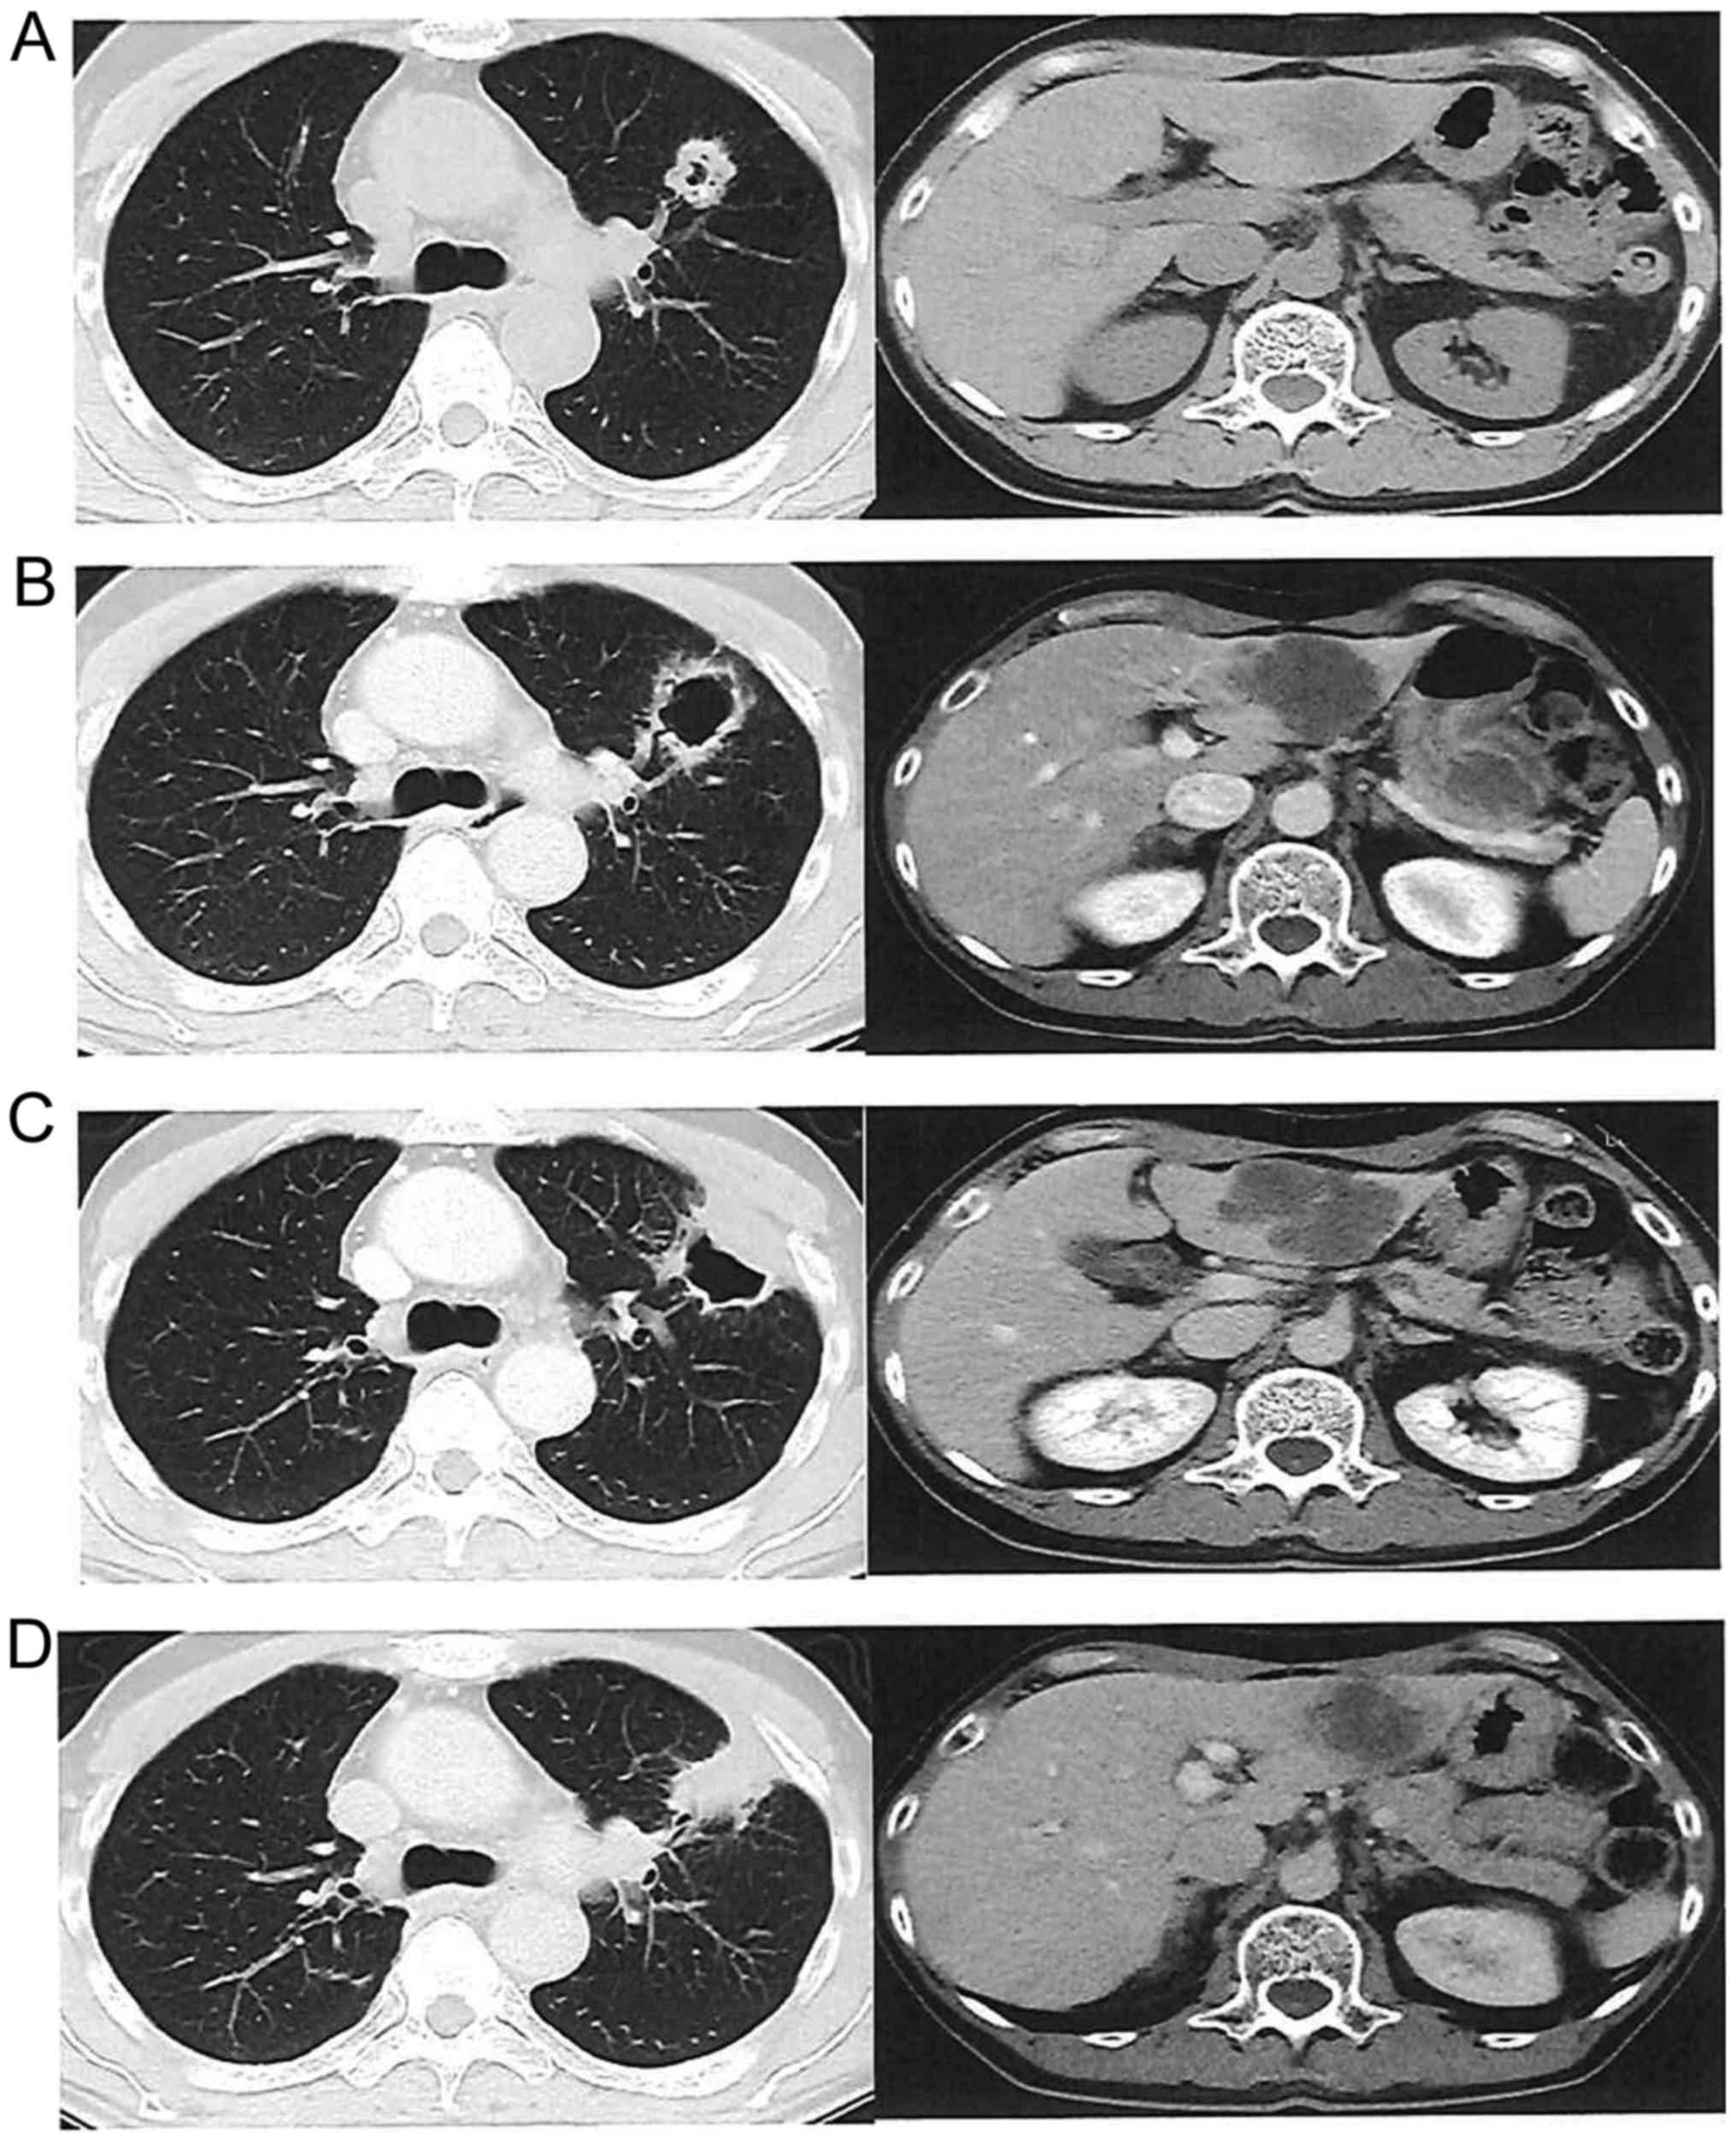

Figure 4.

Efficacy of regorafenib at 120 mg/day in a male patient with lung and liver metastases who received 6 cycles of regorafenib. (A) Pretreatment computed tomography scan. (B) Cavity formation in the lung metastasis, with cystic change of the internal structure in the liver metastases after 2 cycles. (C) Change in size and internal density after 4 cycles. (D) Increased size and internal density of lung and liver metastases after 6 cycles, indicating progressive disease.

None of the patients achieved complete response; however, 1 patient achieved partial response (PR) and 9 had stable disease (SD). The objective response rate was 5.6% and the disease control rate (DCR) was 55.6% (Table III). Two patients who were treated with the dose of 120 mg were able to receive Reg for >6 cycles: One was a 66-year-old woman with local recurrence who received five prior chemotherapies with Bmab, Cmab, panitumumab, L-OHP, CPT-11 and FUs. The patient was started on Reg as sixth-line chemotherapy, and after three courses of Reg, the local recurrence exhibited a PR and the radiological tumor density decreased, with cystic changes of the lesion. The patient was eventually treated with Reg until the ninth cycle (6.5 months) (Fig. 3). The other patient was a 64-year-old man with multiple lung and liver metastases who received five prior chemotherapies; he was also started on Reg as sixth- line chemotherapy and, after two courses of Reg, formation of a cavity in a lung metastasis with intralesional cystic change of the liver metastases were observed. The patient received treatment with Reg until the sixth cycle (5 months) (Fig. 4). The median OS was 204 days (Fig. 2A) and the PFS was 77 days (Fig. 2B) in all the patients.